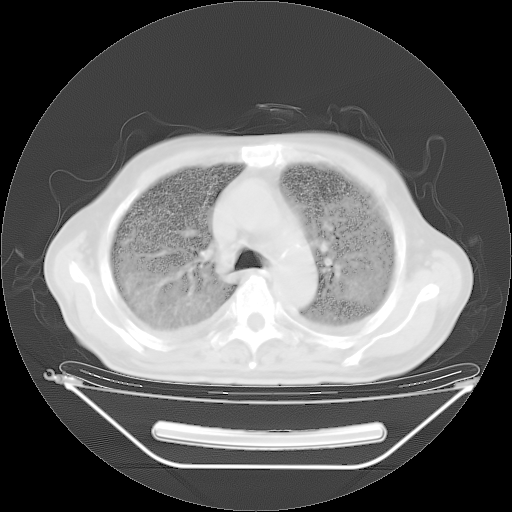

5月9日肺部CT(在4月27日齐鲁医院肺部CT描述部分肺组织磨玻璃样改变,12天后肺组织广泛磨玻璃样改变)

2009年5月9日肺部CT

大致读了系列胸部CT:纵隔窗无明显异常,肺窗:从4、27至今:主要是双肺中下野外带可见毛玻璃样改变,目前处于急性肺泡炎阶段,至于原因考虑1、结替组织或胶原血管性疾病所致?2、恶性疾病如恶组在肺部所致的表现或细支气管肺泡癌?3、药物或其它原因如肺蛋白沉着症所致肺泡炎目前不太可能?总之,明天就去请我院的呼吸科、感染科、血液科和临免专家会诊哈。